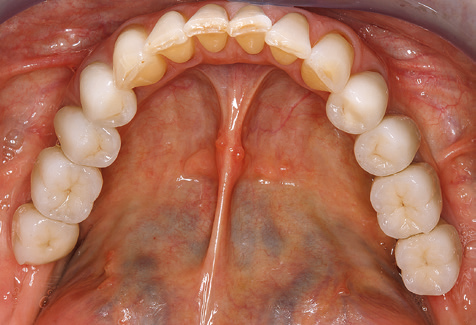

Standardised and regular risk-adapted care in the scope of SPT is the key to treatment success for the clinical long-term success in periodontically compromised patients. This is particularly true for patients fitted with implants following successfully completed periodontal treatment (Fig. 11a and b).

Fig. 9: The accessible implant and tooth surfaces are polished with polishing cups and suitable polishing compounds. – Fig. 10: Repeat instruction in the use of appropriate aids for oral hygiene at home should also form part of SPT. – Fig. 11a and b: Clinical situation 12 years after insertion of the prosthetic restoration. During this period, only a veneering ceramic fracture on tooth 47 and the requirement for endodontic treatment of tooth 12 were observed. All restorations are still functioning as intended.

The ten-year check-up revealed no indications of advancing clinical attachment loss or peri-implant bone substance loss (Fig. 3).

The patient continues to visit the clinic every six months for SIT. In the following, the patient is taken as an example for demonstrating the individual working steps in a structured SPT session as it has been performed with barely any modifications over the last 12 years. Of course, some new materials and devices have been integrated into the concept over the years. This clinical case report presents the current material and device concept.